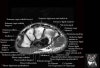

- Axial section

Axial PD fat suppressed evaluates the tendons of the wrist and carpal tunnel, including the median nerve.